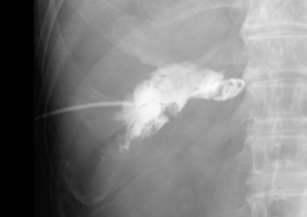

図1 経皮経肝胆嚢ドレナージ(PTGBD)

透視下に胆嚢内にチューブが挿入されている。

胆嚢内には結石を疑う陰影欠損を認める。

腹部超音波(エコー)ガイド下に経皮的に胆嚢を穿刺し、X線透視下にワイヤーガイドでチューブを胆嚢内に留置し、胆嚢内の胆汁を体外に排出します。最も一般的な方法で、成功率が高く治療効果も確実ですが、出血やお腹のなかに胆汁がもれるリスク、お腹からチューブが出るため患者さんの生活の質(QOL)が低下する、いったん留置したチューブはしばらく抜去できないなどの欠点があります。